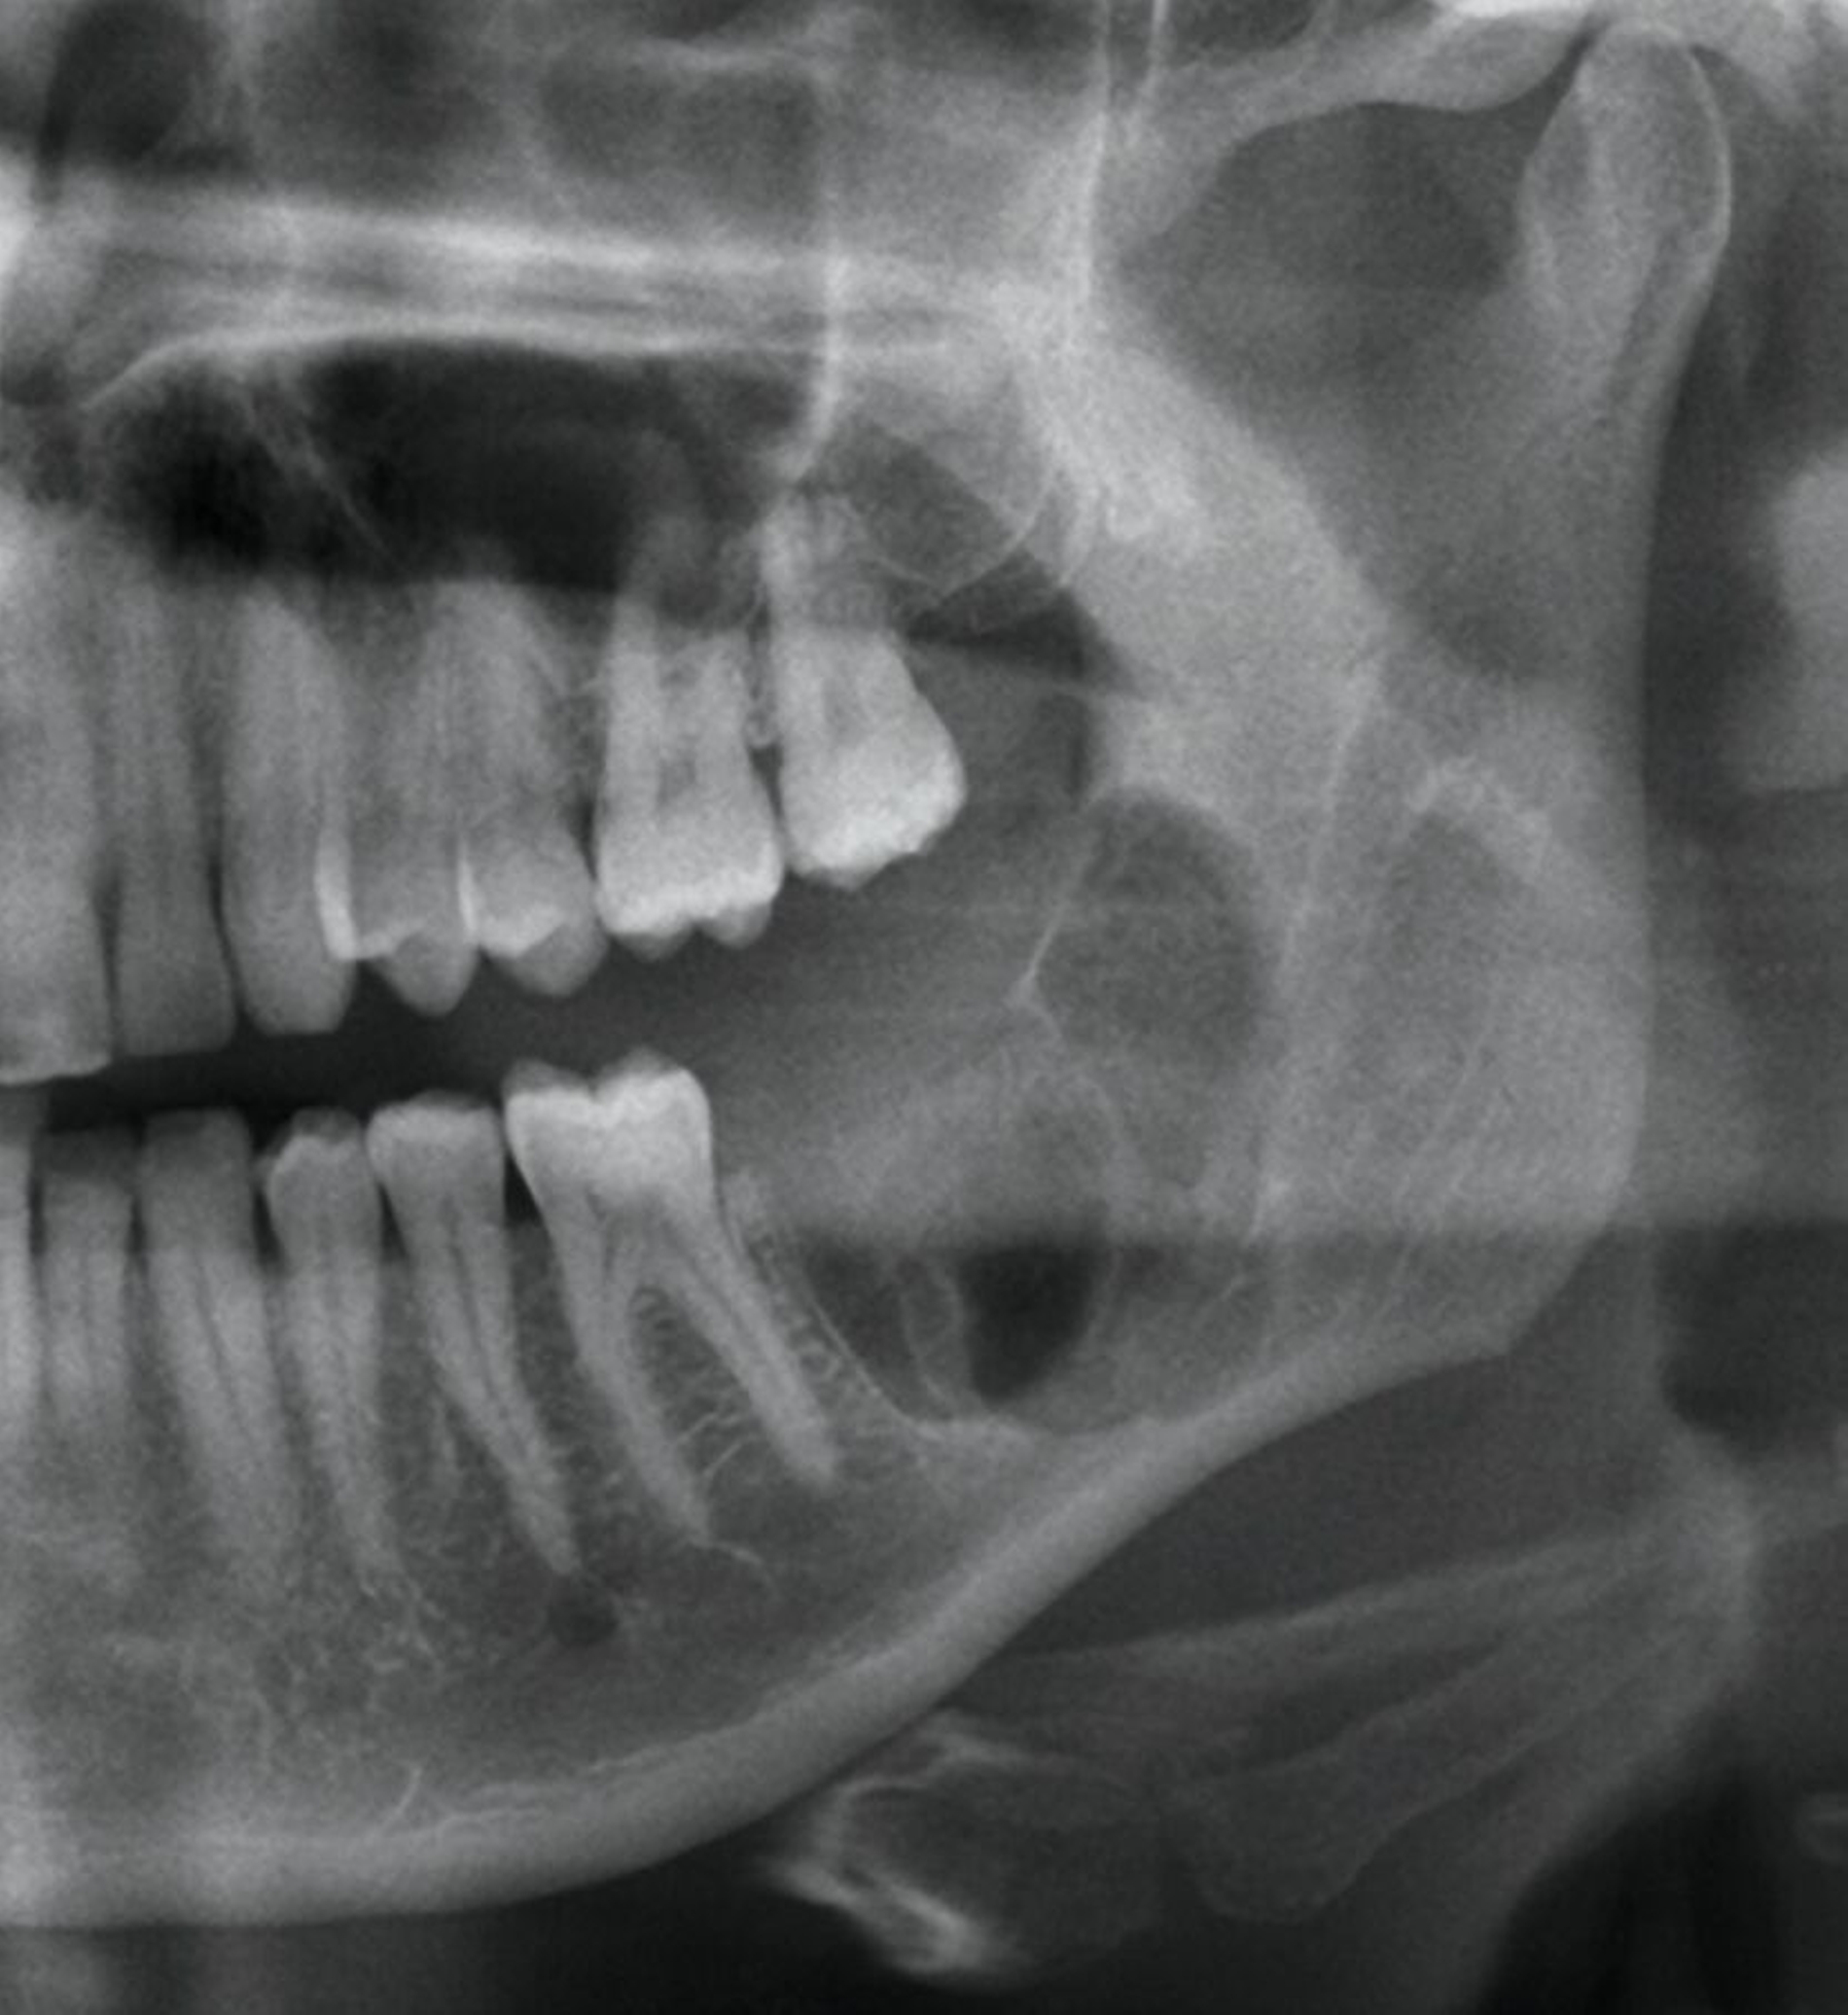

Die digitale Volumentomografie (DVT) ergab eine mehrkammerige, radioluzente Raumforderung, die sich bei erhaltener Kortikalis von der mesialen Wurzel des Zahnes 37 bis in den aufsteigenden Ast des Ramus mandibulae erstreckte (Abbildungen 1 und 2). Aufgrund der Morphologie bestand der Verdacht auf einen keratozystischen odontogenen Tumor, differenzialdiagnostisch auf andere odontogene Tumoren. Nach Aufklärung wurden die Extraktion des nicht erhaltungswürdigen Zahnes 37 sowie die Zystektomie geplant und zwei Wochen später in Intubationsnarkose durchgeführt.

Radiologisch zeigen Ameloblastome meist eine multilokuläre Seifenblasen-ähnliche Osteolyse mit charakteristischer Radioluzenz [Gasparro et al., 2024]. In seltenen Fällen kann auch ein unilokuläres Muster beobachtet werden [Rayamajhi et al., 2022]. Das klinische Erscheinungsbild ist heterogen. Man unterscheidet das konventionelle, das unizystische und das periphere Ameloblastom, wobei die konventionelle Form am häufigsten ist und verschiedene histopathologische Muster aufweisen kann (follikulär, plexiform, akanthomatös oder desmoplastisch) [Haefliger und Baumhoer, 2023].